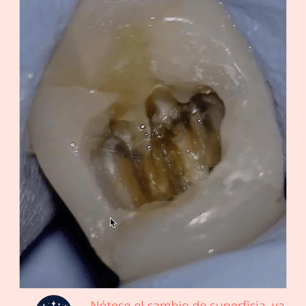

Calcificaciones: Se utilizan instrumentos especiales, como limas ultrasonicas, para localizar y remover las calcificaciones.

Limpieza y Desinfección: El conducto radicular se limpia y desinfecta una vez que las calcificaciones se han eliminado.